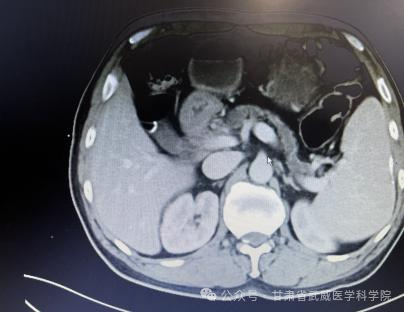

胰腺癌一经确诊没有手术根治机会平均生存期在三个月到半年左右,部分患者能够手术根治切除,术后总体五年生存率不超过5%。本病发病率男性高于女性,男女之比为1.5~2:1,男性患者远较绝经前的妇女多见,绝经后妇女的发病率与男性相仿。胰腺癌诊治困难主要在于其起病隐匿、转移迅速。武威肿瘤医院腹部外科凭借强大的技术力量,近日连续治疗了肝门胆管癌,胰腺癌等数例高难度患者,手术均成功实施,且患者均恢复顺利出院,我科2023年02月收治一例胰头部占位,经科主任仔细阅片、全科讨论后患者胰腺癌肿瘤侵犯门静脉(环周超过1800)及胃十二指肠动脉无外科切除机会,经过术前五周期全身静脉化疗(吉西他滨1000㎎/m2+白蛋白结合型紫杉醇125㎎/m2 D1、8)后CT评估该患者胰腺癌瘤体明显缩小,肿瘤与门静脉主干、胃十二指肠动脉之间有了一定的间隙,与患者家属积极交代病情及沟通后于2023-7-为该患者施行“根治性胰十二指肠切除+I125粒子植入术”,现恢复良好,总生存时间已超过1年。

经过5周期化疗后复查腹部CT资料